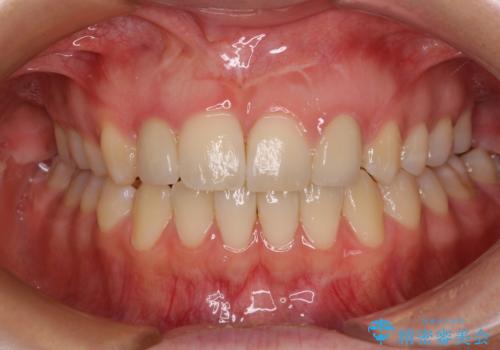

- 他院で矯正治療を終え、上顎前から2番目の歯の大きさを気にして来院された患者様です。

右側は小さく、左側は欠損により犬歯が前から2番に来ている状態でした。

矯正治療の段階で、矮小歯は前後にスペースが作ってあったため、極力左右対称の歯冠形態となるように補綴治療を行うこととしました。

歯根の太さや幅が左右で異なるため、歯肉ラインはどうしても左右非対称となってしまいますが、とても自然な口元となりました。